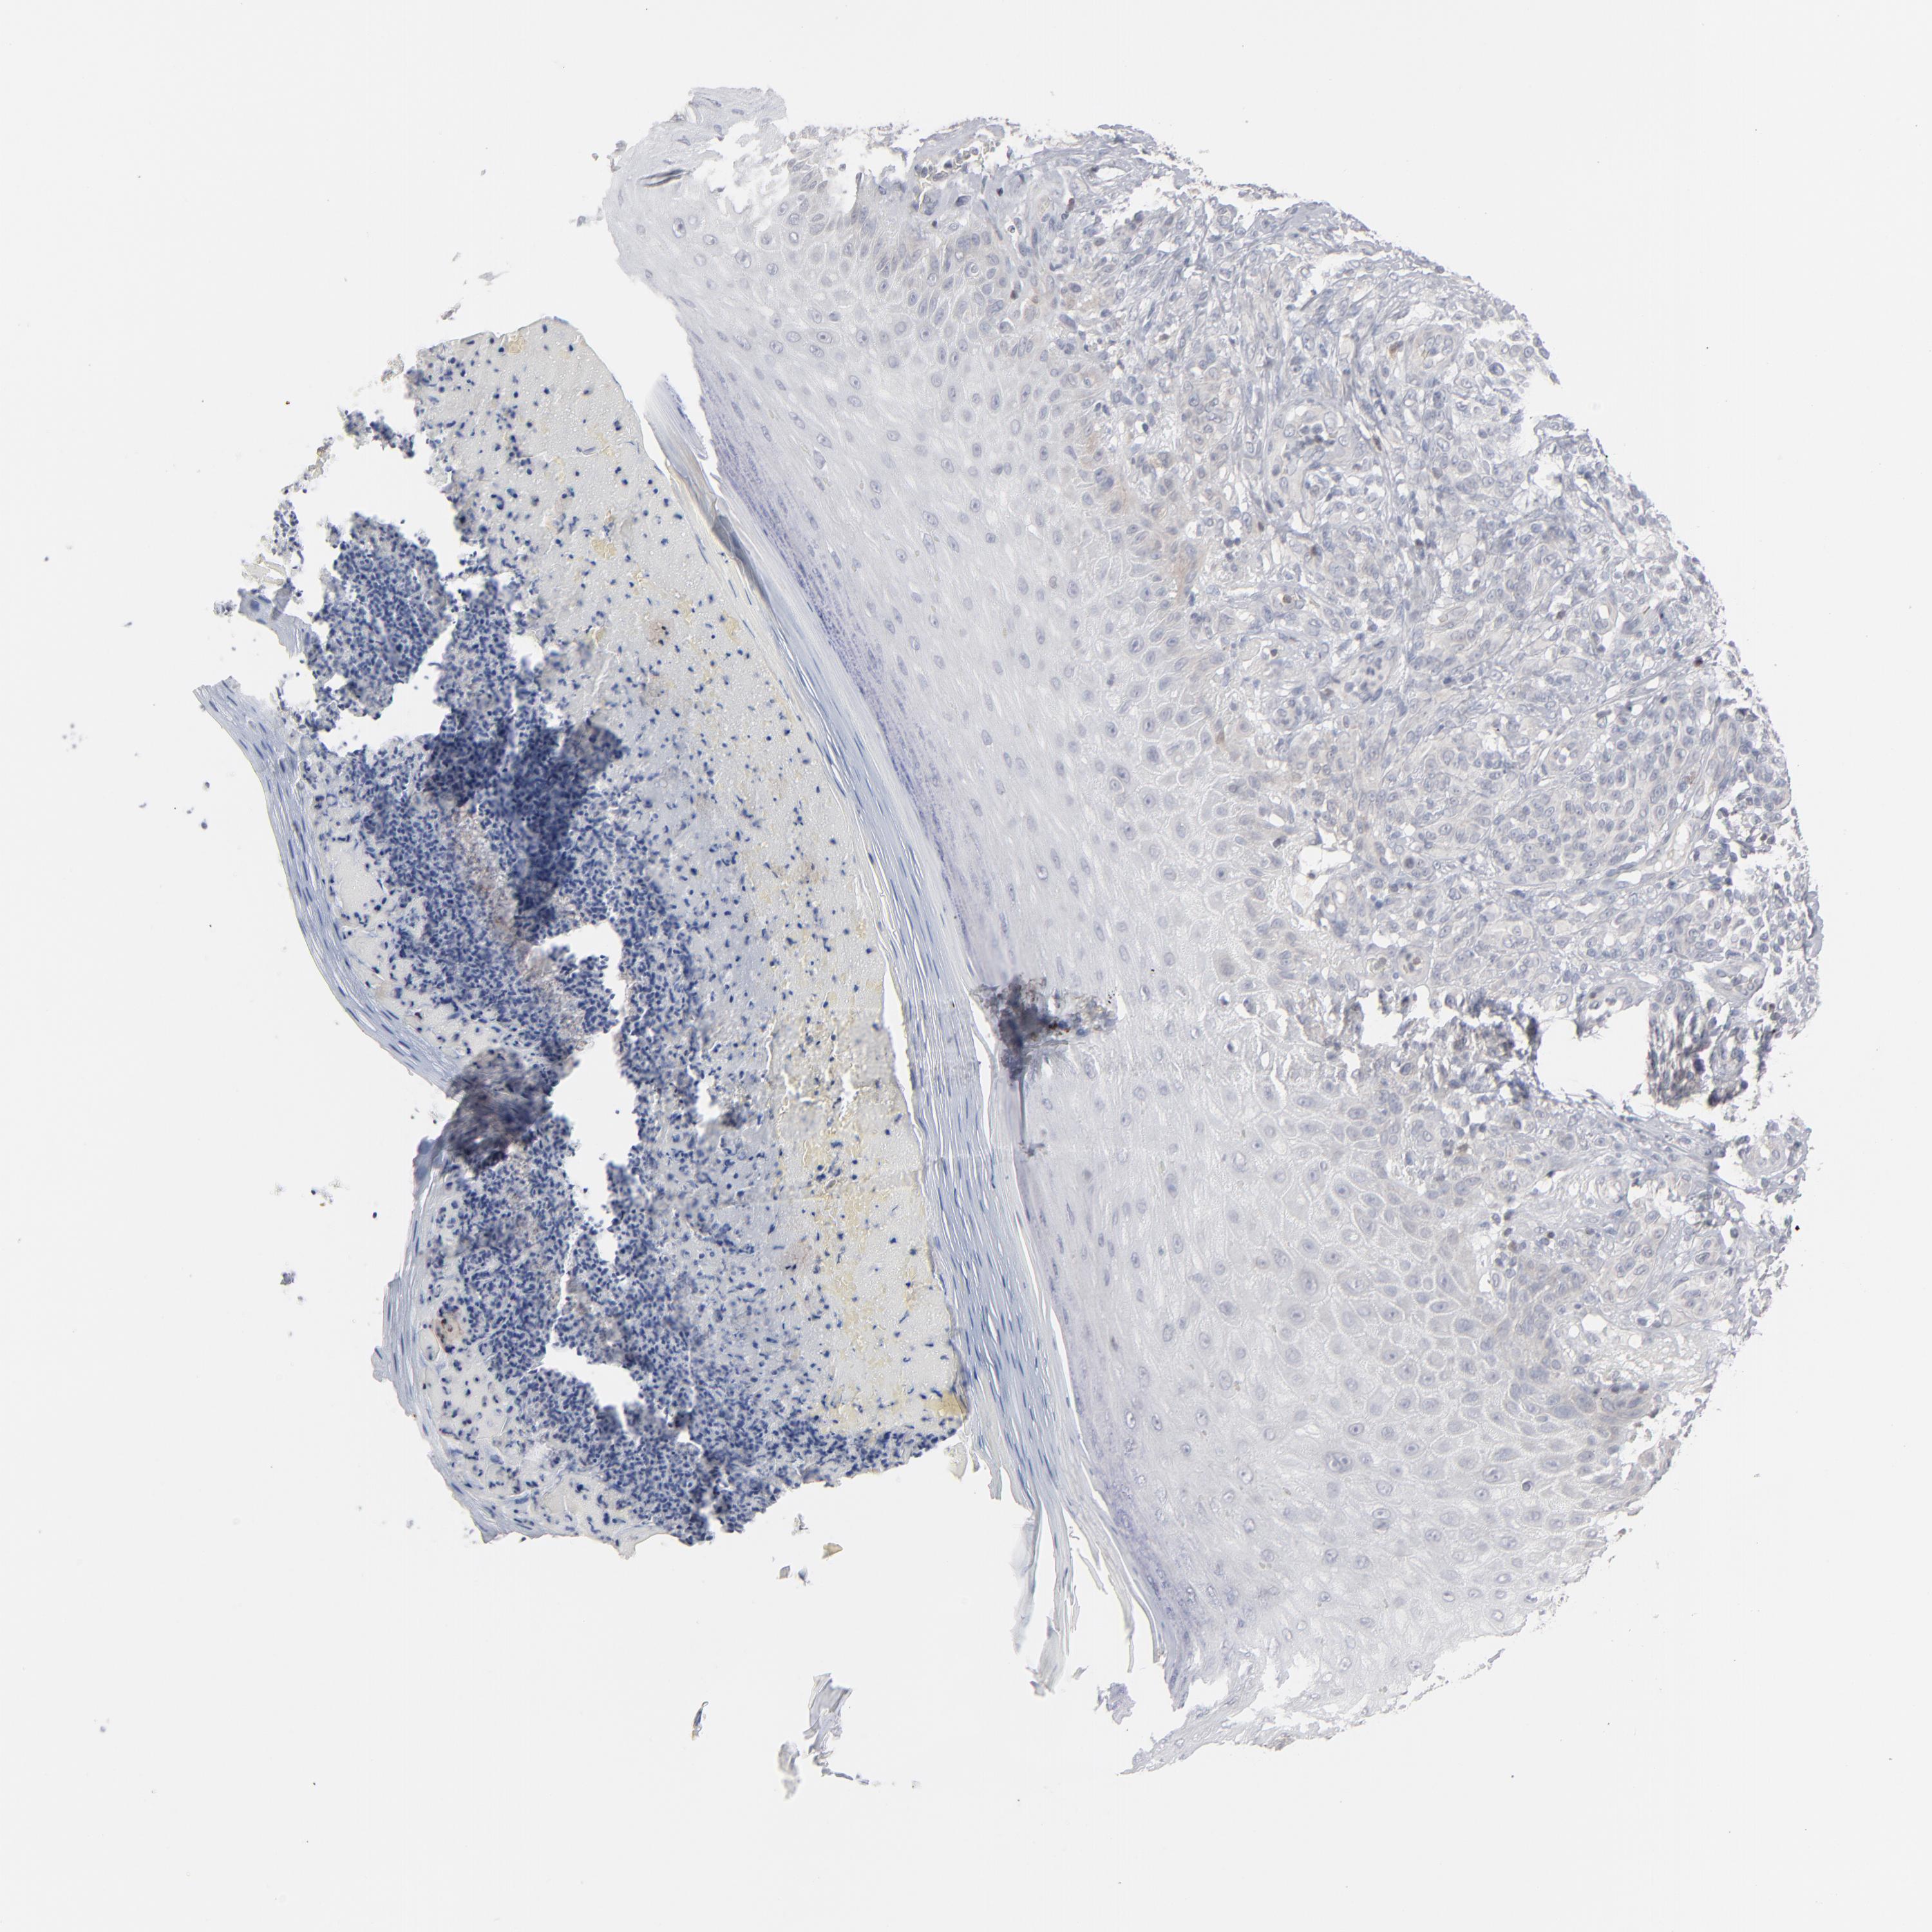

MELANOMA - Protein expressioni

A mouse-over function shows sample information and annotation data. Click on an image to view it in a full screen mode. Samples can be filtered based on level of antibody staining by selecting one or several of the following categories: high, medium, low and not detected. The assay and annotation is described here.

Note that samples used for immunohistochemistry by the Human Protein Atlas do not correspond to samples in the TCGA dataset.

Antibody stainingi

Antibody staining in the annotated cell types in the current human tissue is reported as not detected, low, medium, or high, based on conventional immunohistochemistry profiling in selected tissues. This score is based on the combination of the staining intensity and fraction of stained cells.

Each image is clickable and will lead to virtual microscopy that enables deeper exploration of all samples and also displays staining intensity scores, fraction scores and subcellular localization as well as patient and tissue information for each sample.

Antibody HPA001860

Antibody CAB013108

Staining

High

Medium

Low

Not detected

Intensity

Strong

Moderate

Weak

Negative

Quantity

>75%

75%-25%

<25%

None

Location

Nuclear

Cytoplasmic/membranous

Cytoplasmic/membranous,nuclear

Malignant melanoma, NOS

Malignant melanoma, Metastatic site